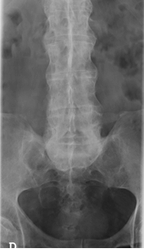

Fig 13 B. Espondilitis anquilosante.

Rx AP de columna. Presencia de sindesmofitos en la columna dorsolumbar.

Compromiso simétrico de ambas articulaciones sacroiliacas, las cuales están fusionadas.